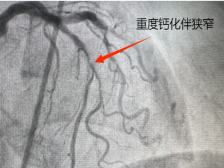

心脏血管长了 “硬石头”?“磨”“震” 联手打通生命通道

2eb9cf3dfa134a66a25800f1d5a3adf9.png?x-oss-process=style/w640)